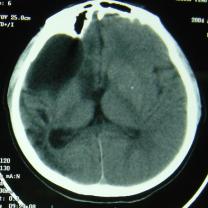

CT检查:右额部见边缘清晰的脑脊液密度区,大小约82mm×52mm,与侧脑室相沟通,内侧达中线,其内可见带状分隔;右侧颞顶叶及部分枕叶脑组织呈低密度改变,左侧侧脑室形态、大小正常,中线结构尚居中(图1)。

图1 CT(①②)显示右额部边缘清晰的脑脊液密度区与侧脑室相沟通,其内可见带状分隔;右侧颞顶叶及部分枕叶脑组织呈低密度改变